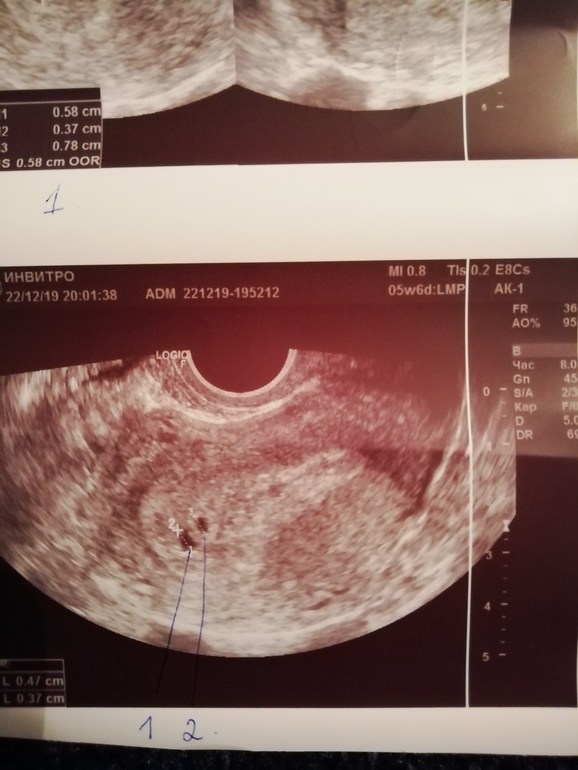

Двойня. Размер ПЯ не соответствует срокам. 😢

Внутриутробное развитие двойни/тройниДевочки дорогие, ситуация такая у меня. 7 циклов планирования и наконец то в 8ом цикле на 12 ДПО я увидела слабенькую вторую. Счастье, трепет. Даже не обратила внимания на светлокоричневую мазню в дни предполагаемых месячных. Сдала хгч на второй день задержки 141,4потом через 2 дня 473, 1. Успокоилась. Но как то потягивало живот и я пошла в ЖК. Там взяли мазок, записали на УЗИ 26.12. и назначила свечи утрожестан 200 на ночь. И я спокойно ждала УЗИ. И сегодня бац и розовая слизь вечером 😟 я собралась и на платное УЗИ побежала. Первое, что ошарашило, это 2 плодных яйца, НО размер их очень не соответствует сроку. По месячным 5 недель 6 дней, по УЗИ 4 недели 3 дня. 😢 Эмбриончиков не видно, а ведь уже сердечко должно стучать. Ещё признаки гематомы под вопросом. В общем врач ничего точно не сказала, предположила неразвивающуюся беременность, а так же позднюю имплатацию. Я не знаю что думать. Завтра пойду в ЖК без записи, надеюсь примут. УЗИ у меня теперь в ЖК 26.12. Прикладываю фото УЗИ. Пожалуйста поделитесь, у кого похожая ситуация была или есть🙏